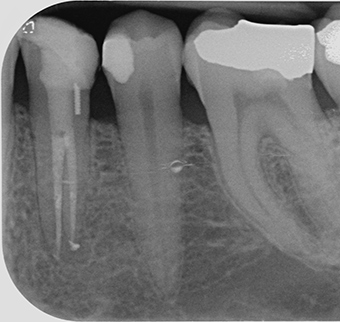

- Fig 1 – Previous GP removed

- Fig 2 – LL4 WL radiograph of buccal canal

- Fig 3 – LL4 WL radiograph of lingual canal

- Fig 4 – LL4 MAC radiograph

- Fig 5 – LL4 final radiograph

- Fig 6 – LL4 one-year review radiograph

The canal was irrigated copiously with 5.25 per cent heated (50 degrees celsius) sodium hypochlorite. Heated sodium hypochlorite was used because research by Cunningham et al 1980, Abou-Rass et al 1981, Gambarini et al 1998 and Sirtes et al 2005 have all shown the enhanced tissue dissolving effects of 5.25 per cent sodium hypochlorite when heated to 45-60°C. A radiograph was then taken to verify the working length (20mm from the occlusal surface reference point) and to confirm gutta percha removal since a zero reading had been achieved (at 20.5mm and 0.5mm deducted to give the correct working length) with an electronic apex locator (EAL) (Morital ZX). The EAL was used since much published research appears to have the aforementioned EAL model as being the gold standard amongst other EAL’s. Kobayashi et al 1995 discussed the accuracy of EAL’s of measuring the working length to 0.5mm of the apical foramen. Many studies have concurred with this study. Patency had also been achieved in the buccalcanal (Fig 2).

The tooth was then assessed with the aid of a surgical operating microscope (Carl Zeiss Pico) at x10 magnification. The remaining gutta percha was removed with the aid of Gooseneck burs and a DG16 probe. To locate the lingual canal which was apparent on the initial radiograph, root dentine was removed with ultrasonics (Satalec P5, Satalec-Acteon Merignac, France) using a Start X size three tip and K1 carbon file (Sybron Endo) used to enter the canal. A working length was established as before and measured with an EAL and verified with another radiograph. The lingual canal was again patent and had a working length of 19mm from the occlusal surface reference point (Fig 3).

Both canals were prepared to length with a pecking motion as per the manufacturers guidelines. A MAC radiograph was taken to verify GP lengths after gauging each canal to an apical width size 25 (MAF) (Fig 4).

The rubber dam was then removed, the occlusion checked in ICP and lateral excursions and the surface polished with rubber cups and diamond polishing paste. A final radiograph was taken showing a well-condensed obturation with good coronal, mid and apical seal. Some sealer extrusion was noted (Fig 5).

At a one-year review appointment the patient reported no symptoms and he was delighted at how quickly the tooth had settled post-treatment. Clinical examination reported no significant findings (no soft tissue swelling or tenderness to percussion). The radiograph taken (Fig 6) shows signs of radiographic healing since the radiolucency visible on the pre-operative radiograph is not present. Interestingly, there appears to be some sealer present mid canal on either one or both canals. This may be a lateral canal(s) which was not evident from the initial post-op radiograph taken a year ago. Again, some sealer extrusion is noted in the lingual canal. The definitive restoration was also functioning well.